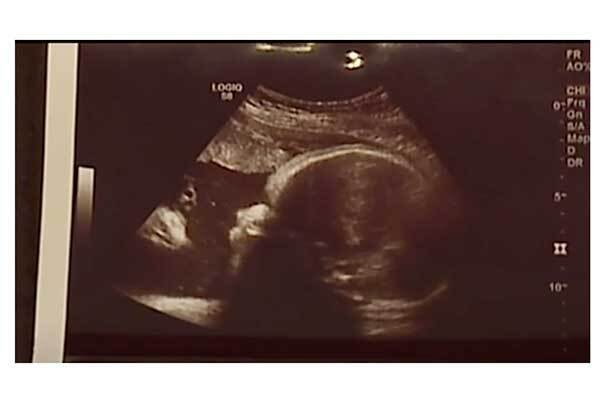

米ペンシルベニア州に住むザック・スミスさんとその婚約者アリシア・ジークさんは第三子の出産を目前に控え、病院で子宮内エコーを撮った。そこには、赤ちゃんと彼女を見つめるイエス・キリストが写っていたそうだ。

「明らかに、娘を見ている顔が写っていました。気づいた瞬間泣きそうになりましたね。信じられません」とスミスさんは地元テレビ局FOX43に語る。

そんな経験を経たがゆえに、第三子のエコーに写ったキリストのような影を、2人は瑞兆だと受け取っている。スミスさんはFacebookで「天使か神か救世主か、何であれこれは祝福のしるしです!」とこの写真をシェア。安産であることを祈りたい。